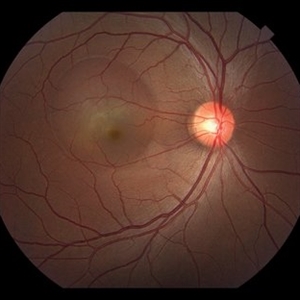

Collateral Vessels in Resolved HRVO

Feb 12 2018 by John S. King, MD

Initial presentation: 25-year-old AAM; Hx DM, Sarcoidosis, Renal Disease, HTN with recent hypertensive crisis. Collateral vessels likely due to old HRVO with one front of NVE inferiorly; veins attenuated proximal to the collateral vessels.

Condition/keywords: collaterals, hemicentral retinal vein occlusion, retinal neovascularization